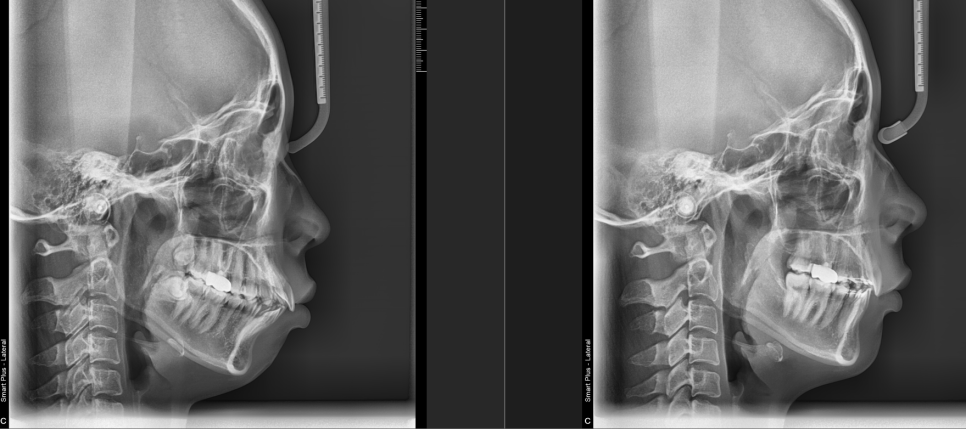

이번에는 케이스를 를보여드릴꼐요

왼쪽이 비포, 오른쪽이 애프터 입니다.

소구치 4개 발치하고 진행한 케이스로, 입이 많이 들어가고, 무턱처럼 럼보이던 것도 더 개선이 된것을 확인할 수 있습니다.

이때 입술 긴장도 역시 줄어들어서 입을 다물기도 더 편안해진 것을 확인할수 있습니다.

환자분은 만족해 하셨고, 저 또한 뿌듯했던 케이스 입니다.